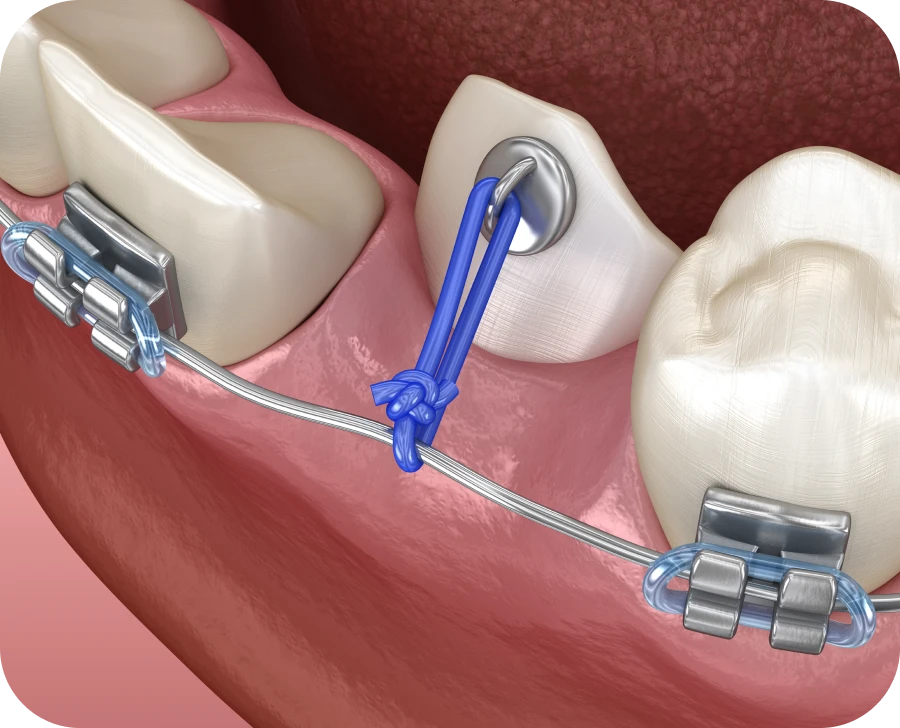

Par la suite, une traction orthodontique est souvent mise en place. Une attache est alors fixée sur la dent, qui est doucement guidée à l’aide d’un fil. Il convient d’ajuster progressivement la force de traction afin de ne pas fragiliser la racine. Des rendez-vous réguliers permettent de suivre l’évolution et de réajuster le traitement si besoin.

Certaines dents sont plus souvent concernées par une inclusion. C’est notamment le cas des canines maxillaires. Leur éruption doit être surveillée dès l’âge de 9 ans. Lorsqu’elles sont orientées vers le palais, une désinclusion chirurgicale est souvent nécessaire. Un traitement interceptif permet alors de dégager leur chemin d’éruption. Une fois la dent exposée, une attache collée permet de guider sa progression vers la bonne position.

Les incisives centrales, en particulier celles de la mâchoire supérieure, peuvent également rester bloquées. Dès l’âge de 7 ans, toute asymétrie dans leur éruption doit faire l’objet d’une attention particulière. Si une incisive semble absente, il convient de rechercher une dent surnuméraire ou un kyste pouvant faire obstacle. Après extraction de l’obstacle, il est parfois possible d’attendre une éruption spontanée. Toutefois, si celle-ci ne survient pas dans les six mois, une traction orthodontique doit être envisagée sans tarder.